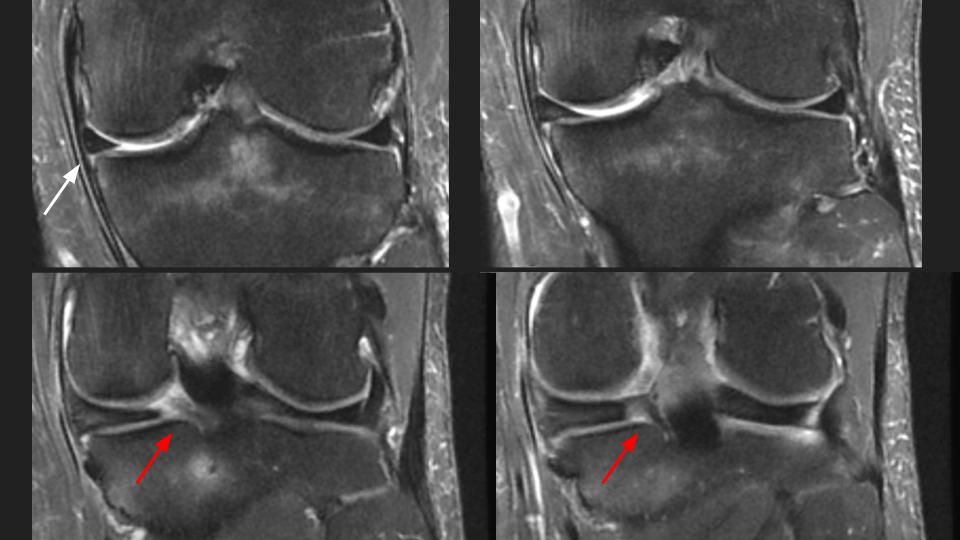

49M runner with pain since twisting injury during marathon 1 year ago

There is a radial tear / avulsion of the posterior horn medial meniscal root (red arrow), which is likely related to the running injury 1 year ago. There is stress related marrow edema, but it is not localized deep to the root anchor. There is 3mm (borderline) extrusion of the medial meniscal body (white arrow), but there is surprising preservation of the medial compartment articular cartilage. Meniscal root tear is known to predispose to medial compartment cartilage loss, which is often rapid. Hes obviously symptomatic and has stress related marrow edema, but why hasnt he developed medial compartment OA?

posterior horn of medial meniscus ( RID2776 )